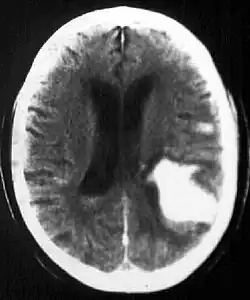

| Multiple intraparenchymal hemorrhage | |

Intraparenchymal hemorrhage is one form of intracerebral bleeding in which there is bleeding within brain parenchyma. The other form is intraventricular hemorrhage).[1]

Computed tomography (CT scan): A CT scan may be normal if it is done soon after the onset of symptoms. A CT scan is the best test to look for bleeding in or around your brain. In some hospitals, a perfusion CT scan may be done to see where the blood is flowing and not flowing in your brain.